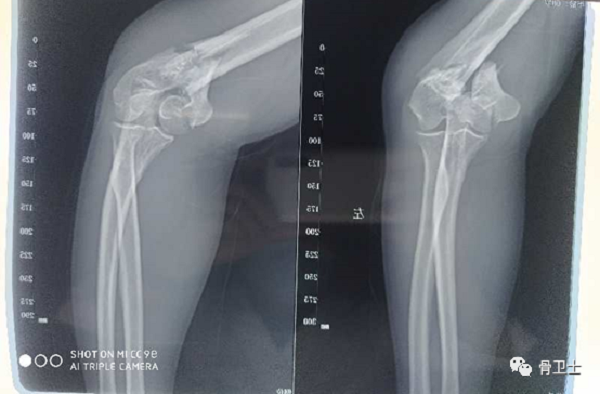

影像检查:左肘关节DR、CT示左肱骨远端粉碎性骨折

6.png

7.png